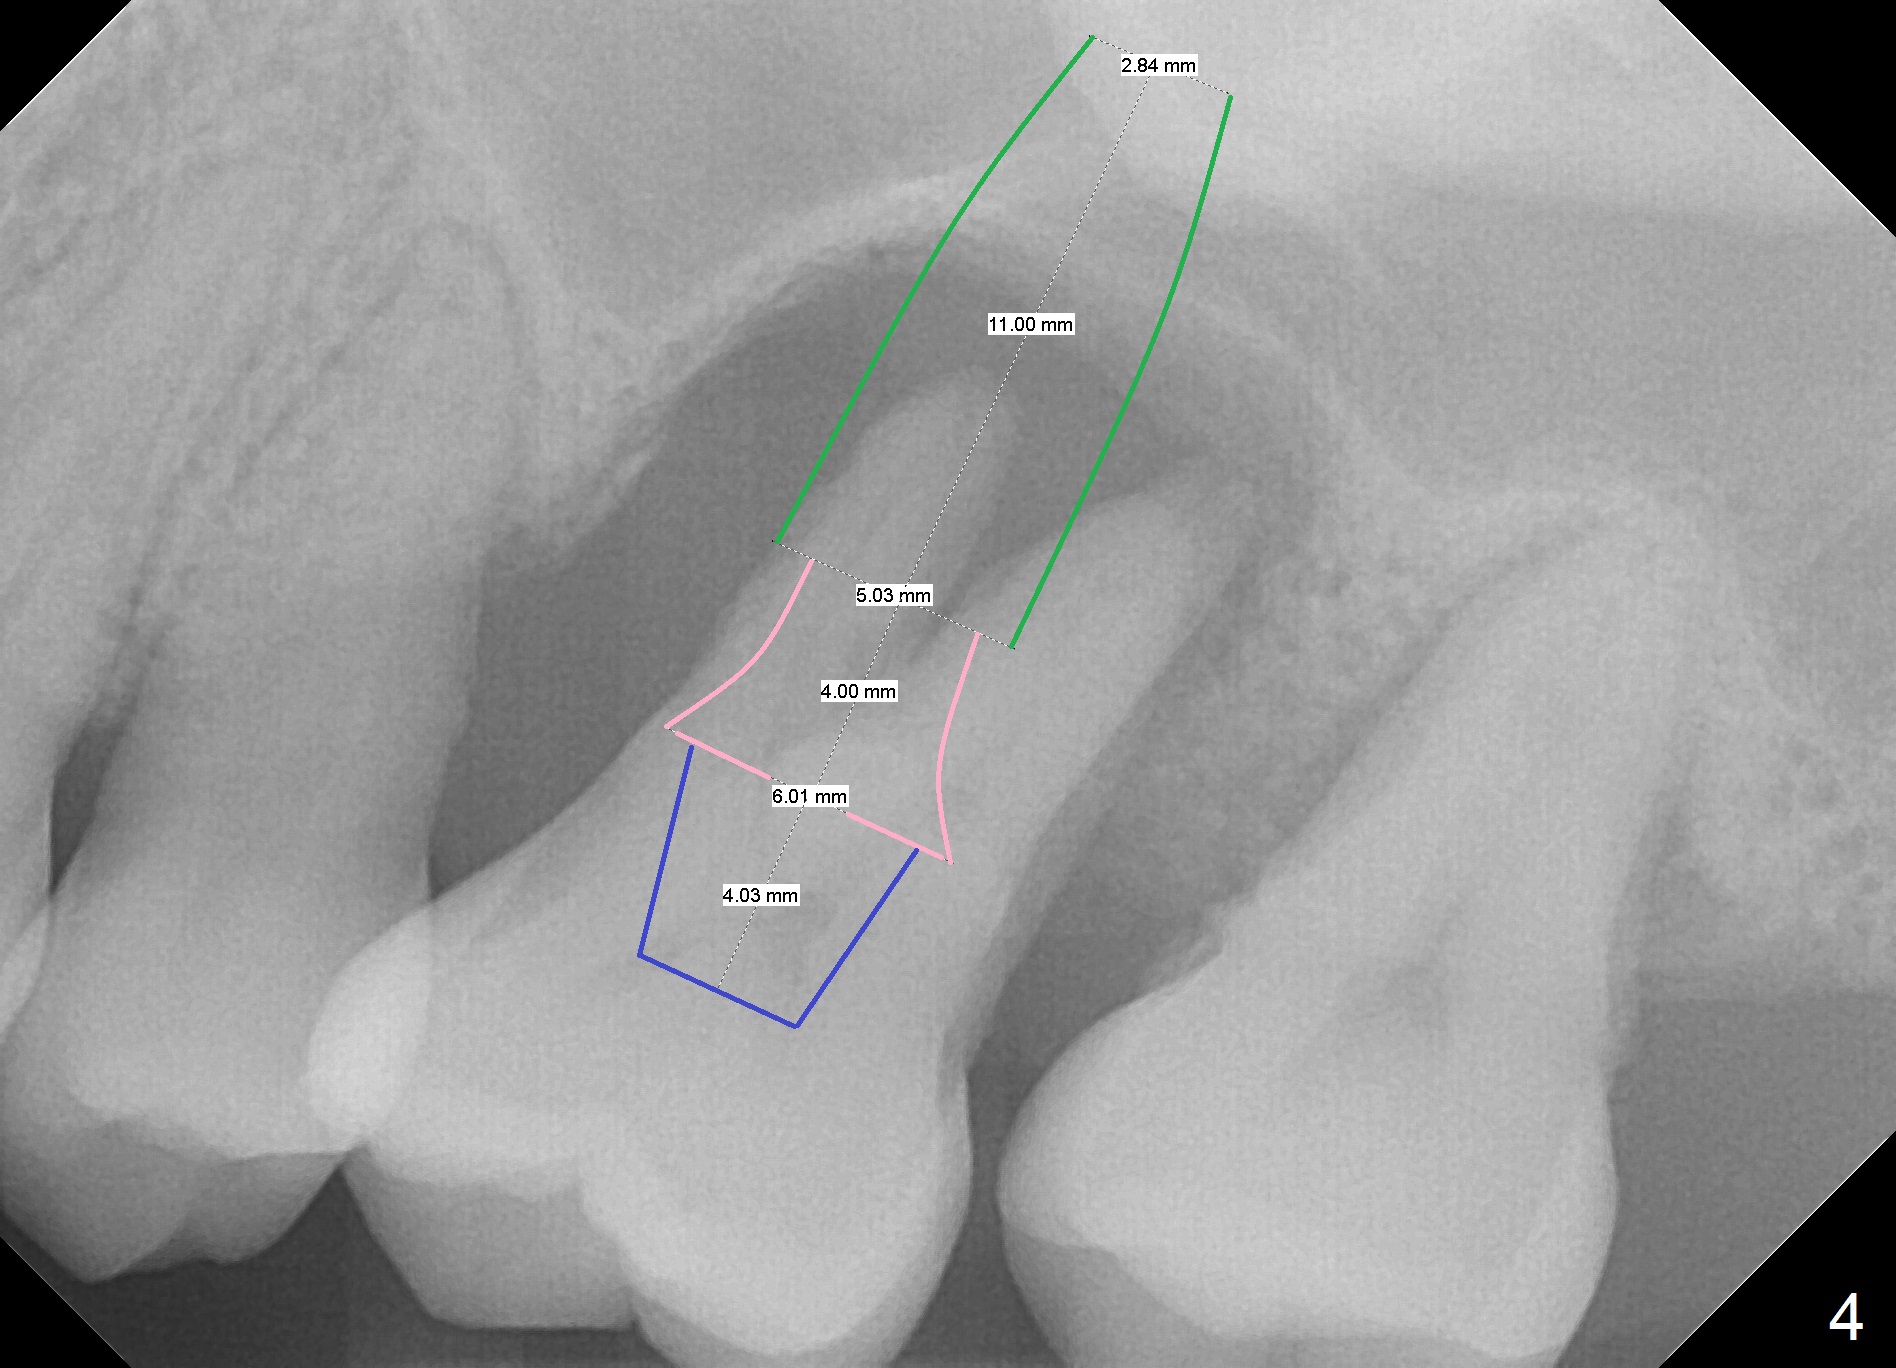

A 41-year-old man has had severe periodontitis at #14 for the last 11 years (Fig.1-3). Finally the tooth is mobile. Draw blood for PRF membrane (x4). After use of Magic Drill with 3 mm stopper, tap Magic Lifter for sinus lift. Insert 1-2 PRF membrane(s) and Vanilla graft prior to further osteotomy with UF drills until 4.5 or 5 mm. Insert tap drill for primary stability. If it fails, switch to IBS dummy implants.